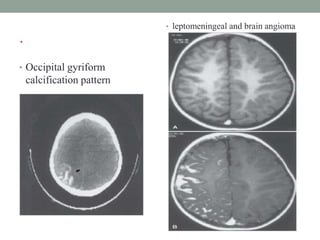

• Occipital gyriform

calcification pattern

• leptomeningeal and brain angioma